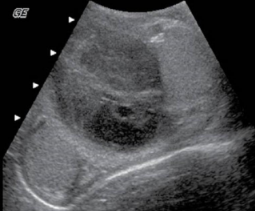

hydroceles are a collection of _____ fluid with painless swelling, and commonly associated with epididymo-orchitis and torsion

assoc findings of epididymo-orchitis

scrotal wall thickening and hydrocele (low level or anechoic echoes) in the anterolateral area of testes